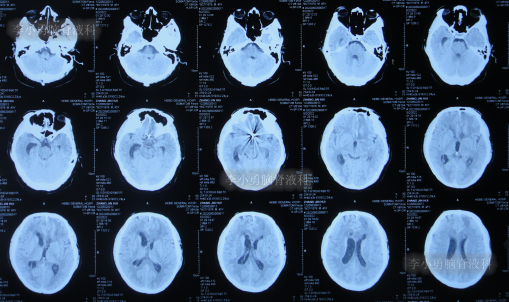

脑动脉瘤栓塞术后4天即2022年7月12日,查头颅CT示仍有积血(图-4)。

图-4:2022年7月12日头颅CT

拔除引流管后10天即2022年7月25日(脑动脉瘤栓塞术后17天),查头颅CT示脑室周水肿,仍有少量积血(图-5);仍间断发热,且脑脊液白细胞仍高,脑脊液浑浊。

图-5:2022年7月25日头颅CT